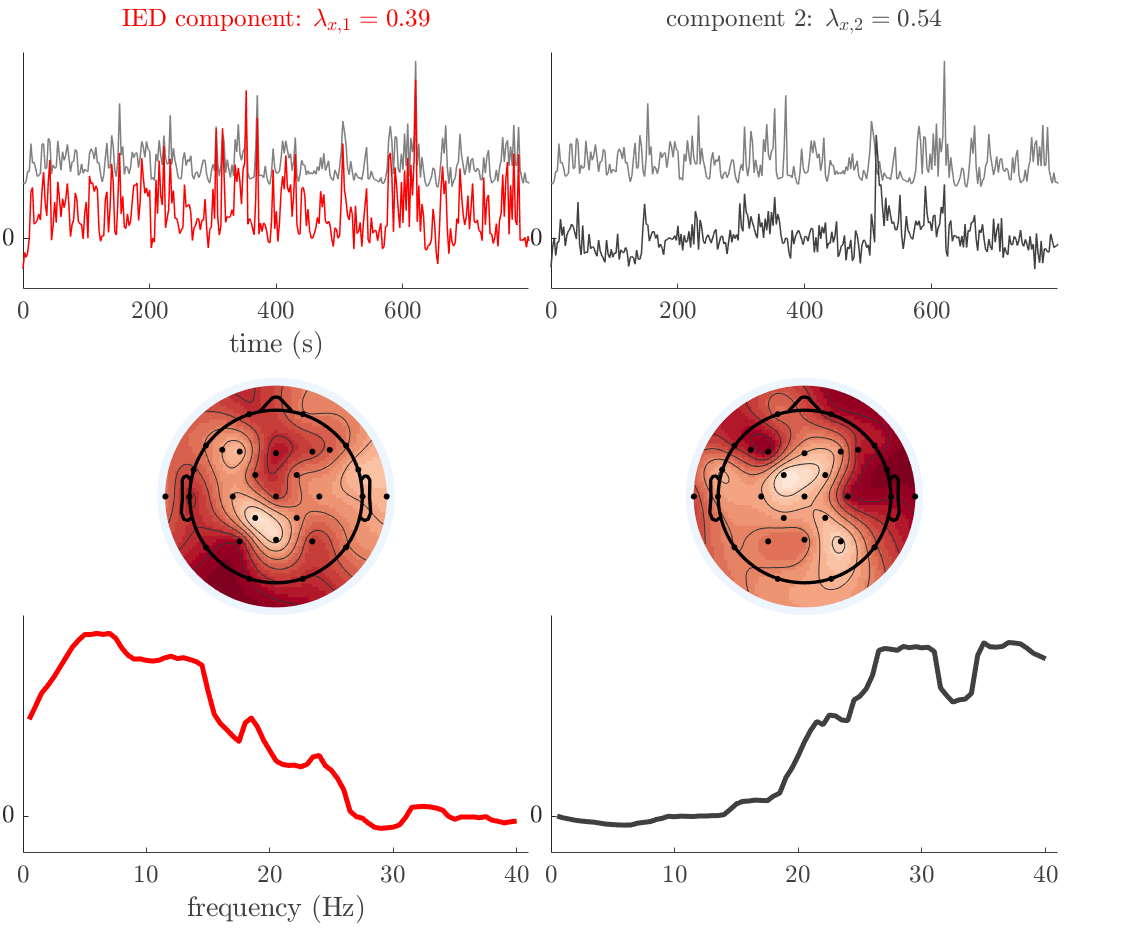

Patient 2

We analyze the solution with sources, and show the results in Figure 3 and 4. As for patient 1, we found a source which is strongly correlated to the MWF envelope, and which had a mostly low-frequency behavior characteristic for spikes. The topography is mostly uninformative, and does not clearly correspond to the patient’s clinical data. The third source is mostly present at both sides of the head, is very sparsely active in time, and has a high-frequency content: this is most likely an artifact due to the neck muscles. Again, there is one of the highest-entropy HRFs which belongs to a ROI in the IOZ. Now, the waveform is clearly resolved from the other HRFs, through the strong initial dip (before 0 seconds). Such a dip is sometimes observed in HRFs, but its underlying physiological mechanism is not yet fully understood. It is possible that this dip reflects altered vascular autoregulation near the IOZ (cfr. the explanation in the Section 1 of the main text), or a rapid depletion in oxygen due to IED generation (before the IED becomes visible on the EEG). Figure 4 furthermore shows that the IED-related component is significantly active in parts of the IOZ, and deactive in others. As mentioned earlier, this deactivation may or may not be due to errors in sign correction. Interestingly, the ROI with the high alteration in neurovascular coupling is distinct from both the activated and deactivated ROIs.